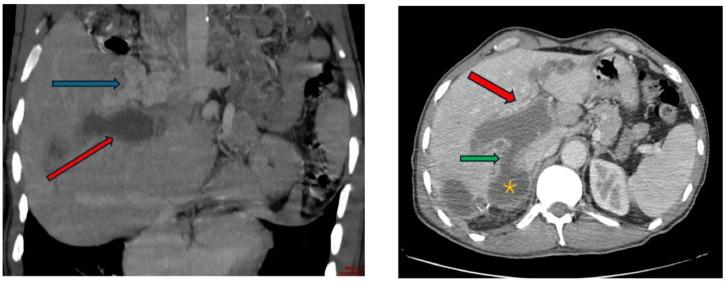

肝包虫囊肿破入门静脉:一种罕见的并发症。

Hydatid cyst of the liver rupturing into the portal vein: A rare complication.

Hydatid cyst of the liver is a zoonosis caused by parasite , which remains highly prevalent in Morocco. Current medical imaging modalities, particularly ultrasonography (US) and computed tomography (CT), facilitate rapid and accurate diagnosis, enable effective treatment possibilities and allow for easy follow-up. Complications are typically dominated by infection and rupture, especially in the bile ducts, peritoneal cavity, and chest. Dissemination and development within vascular structures, especially the portal vein, are much less common. This underscores the significance of our case, which illustrates this rare complication of hydatid cyst of the liver.

摘要

肝包虫囊肿是一种由寄生虫引起的人畜共患病,在摩洛哥仍然高度流行。当前的医学成像方式,尤其是超声检查(US)和计算机断层扫描(CT),有助于快速准确的诊断,提供有效的治疗可能性并便于随访。并发症通常以感染和破裂为主,尤其是在胆管、腹腔和胸部。在血管结构内,尤其是门静脉内的播散和发展则要少见得多。这凸显了我们病例的重要性,该病例说明了肝包虫囊肿这种罕见的并发症。